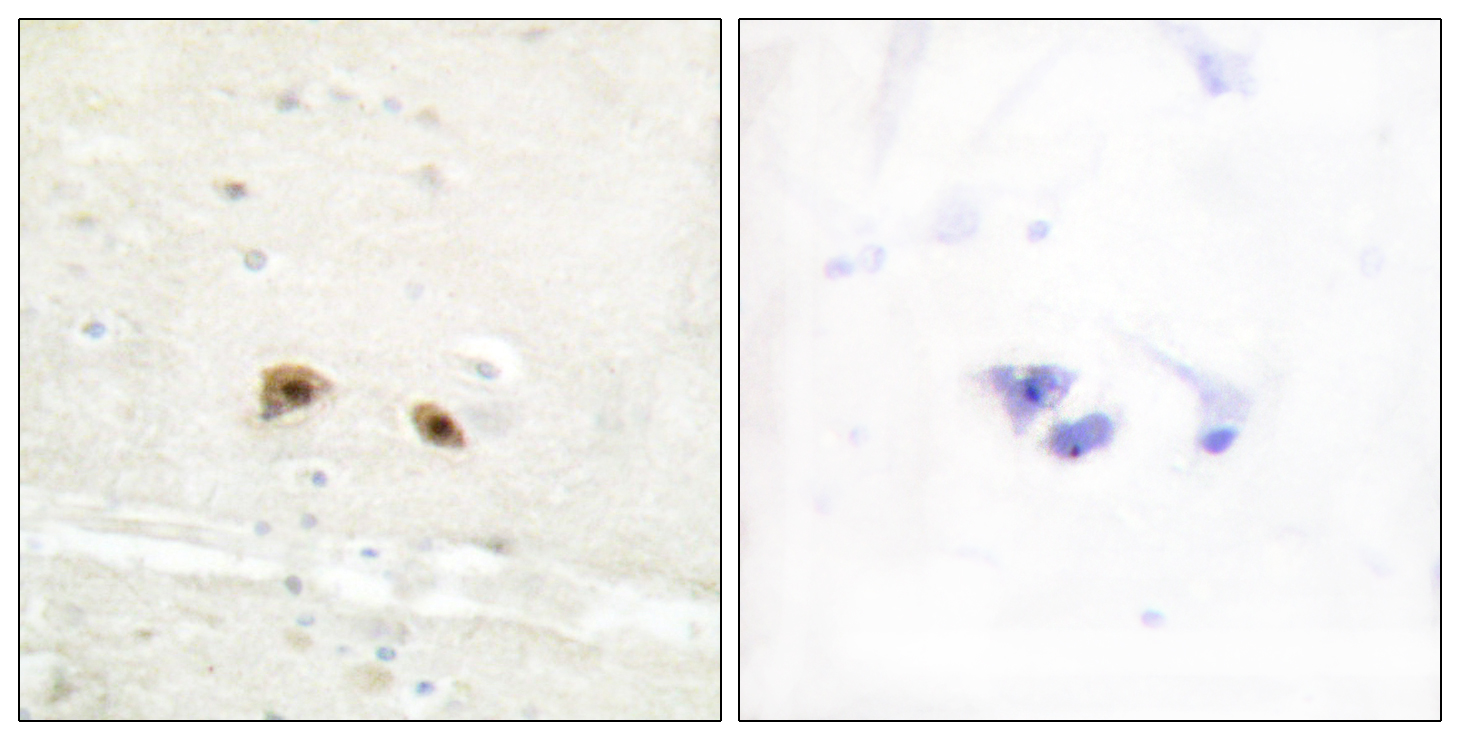

Anti-GJA3 AntibodyA97784

ApplicationsELISA, ImmunoHistoChemistry

ReactivityHuman, Mouse, Rat

Anti-Elk1 AntibodyA97785

ApplicationsELISA, ImmunoHistoChemistry

ReactivityHuman, Mouse, Rat